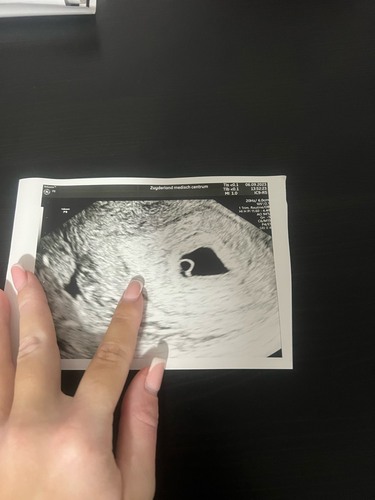

Dit was mijn echo na 6 weken. Ze durfde niet zeker te zeggen dat er een embryo zat, was nog wat twijfelachtig. Over 1 week een nieuwe echo. Hopelijk dan een embryo en sterk kloppend hartje te zien🙏🤞

Bij mij precies hetzelfde volgens mijn berekening zou ik 8 weken moeten zijn maar VK zag alleen dooierzakje en vruchtwater zakje